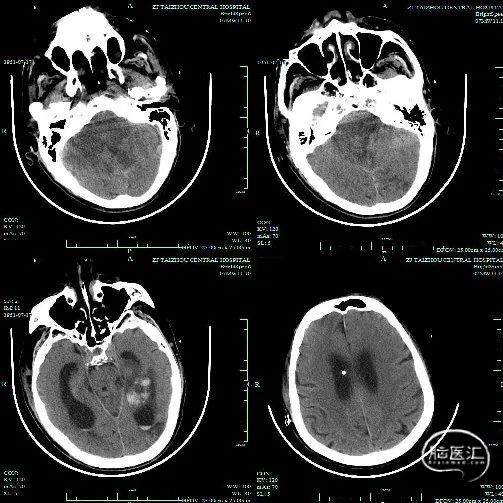

头颅CT

本例患者发病时间明确,后循环梗死发病时间较短,有明确的手术适应症。

本例手术中较大的难点在于取出P2段的血栓,如选择支架在该位置相对不易取出血栓,且风险较高,而选择3Max抽吸导管到位简单、安全,抽吸出的血栓也较为完整,是手术成功的一个重要要素。